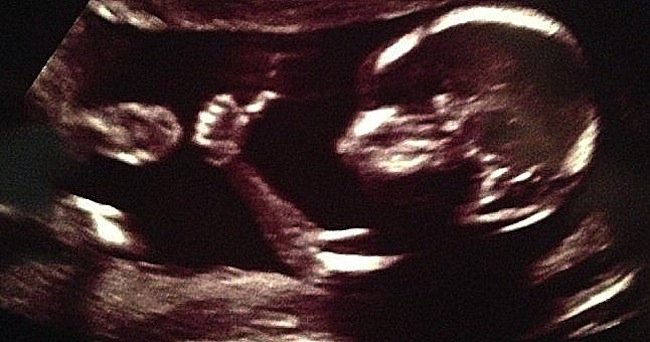

The women, who will have been on a waiting list, will receive a womb from a patient who has been pronounced brain dead, but whose heart has continued to beat. This is known as a living donor. The organ would then be transported to the recipient who would undergo an operation taking about six hours. Following monitoring lasting approximately a year, doctors will implant an embryo into the womb, a combination of the woman's eggs and her partner's sperm. If successful, once a baby is born, the woman would have to have the womb removed. This is because whist a woman lives with a donated womb, they must stay on very strong immunosuppressive drugs. What a great development for both men and women!